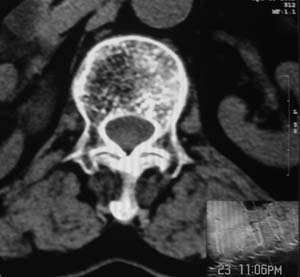

患者,女,72岁,胸背部疼痛3月余,无明显外伤史。曾应用局部封闭、非甾体类止痛药治疗效果不明显,近来疼痛缓解频感背困,平卧缓解,近日行ct检查发现胸12椎体病变,烦请同道发表意见,诊断什么?有何治疗经验!谢谢!!!

标绘图示:第十二胸椎级第一腰椎椎体楔形改变。ct扫描示:第十二胸椎椎体骨质结构紊乱,并可见一囊状低密度影,边缘可见硬化,椎体皮质完整。

考虑:第十二胸椎陈旧性骨折、许莫氏结节。